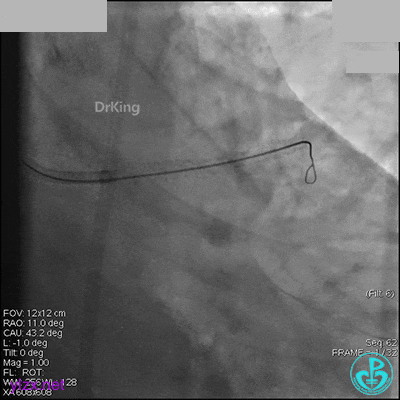

AL 1.0指引导管到位,简单短时尝试导丝不能顺利通过前降支或回旋支病变。改变策略处理右冠脉病变,计划植入2枚支架。AL指引导管到位,Sion blue导丝到达右冠脉远端。导丝通过后1.5mm及2.5mm球囊14~16atm充分扩张中段病变。

右冠脉中段充分扩张后欲植入3.5×38mm支架时,支架难以通过中远段扭曲处,且指引导管、导丝弹出飞扬。反复尝试导丝重新到达右冠脉远端时通过不顺利,局部造影剂滞留,远端血流接近3级。